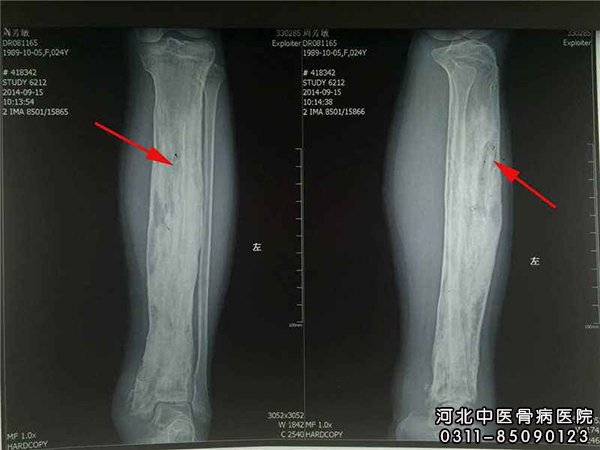

一、X线检查:X线变化在感染后3~4周出现,表现为骨质不规则增厚和硬化,有残留的骨吸收区或空洞,其中可有大小不等的死骨,有时看不到骨髓腔。小骨腔和小死骨在硬化骨中有的不能显影,所以实际存在的数目往往比照片上所显示的多。